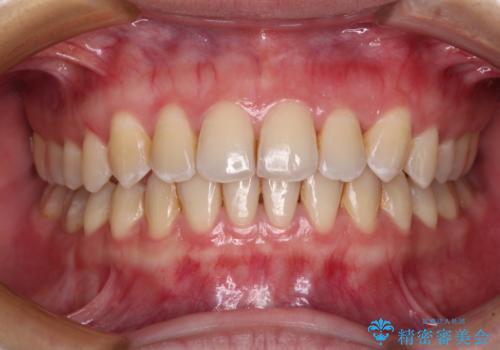

前歯のクロスバイトを短期間で解消 目立たないワイヤー矯正

前歯が反対に咬んでいる インビザラインによる矯正治療